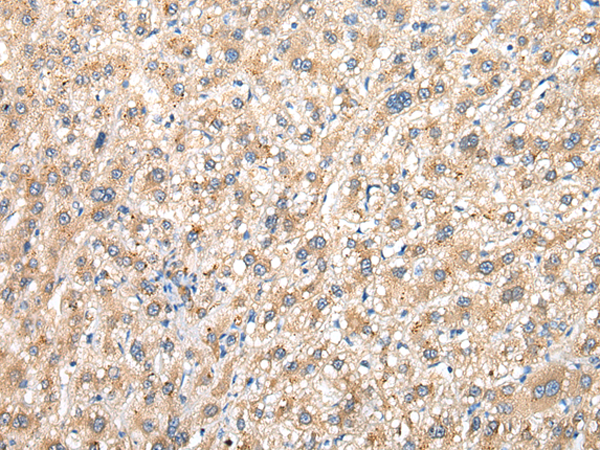

分类: 科研抗体货号: P02144别名:应用: WB,IHC反应种属: Human, Mouse